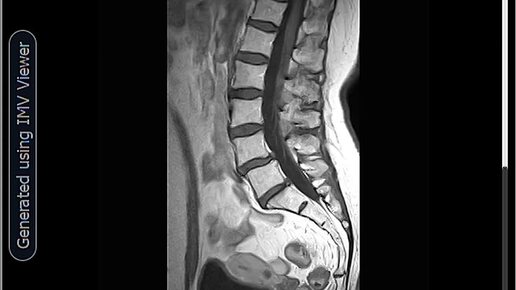

Невринома позвоночного канала